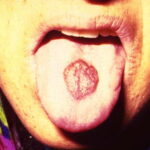

disease onset and have a tendency for rapid progression. In contrast to other variants of KS, the initial lesions in AIDS patients frequently develop on the face, especially on the nose, eyelids, and ears, and on the trunk, where the lesions follow the relaxed skin tension lines . If untreated, disseminated AIDS-KS lesions may coalesce to form large plaques involving large areas of the face, the trunk, or extremities and lead to functional impairments. The oral mucosa is frequently involved and represents the presenting site in 10 percent to 15 percent of AIDS KS . Involvement of the pharynx is not uncommon and may result in difficulty eating, speaking, and breathing.